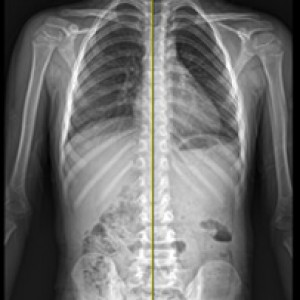

검사부터 다른 당당

“당당은 뼈만 보지 않습니다.”

근육과 근막의 정렬을 함께 진단하며, 풀 스파인 촬영을 통해 머리부터 모든 고관절, 발의 정렬까지 함께 파악하여 개개인에 맞는 전신 치료법을 설계합니다.

전신 엑스레이 검사